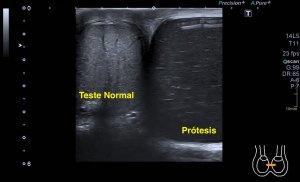

Al llegar al compartimento 6 me encuentro un tendón engrosado de tamaño y aspecto heterogéneo típico de afectación por tendinosis, con líquido en la vaina, te lo señala la imagen con flecha amarilla. Lo recorro y confirmo los hallazgos eje corto y eje largo, hago medidas y compruebo el doppler que marca Neovascularización asociada.

Observa las tres imágenes superiores, son muy ilustrativas, son comparativas de normalidad hallazgos patológicos, el izquierdo claramente patológico y el derecho claramente normal.